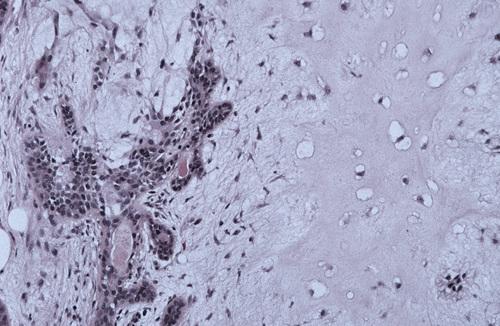

Necrotic mucous acini (left) and adjacent ductal squamous metaplasia (right). The overall lobular architecture of the involved glands is still preserved.

necrotizing sialometaplasia